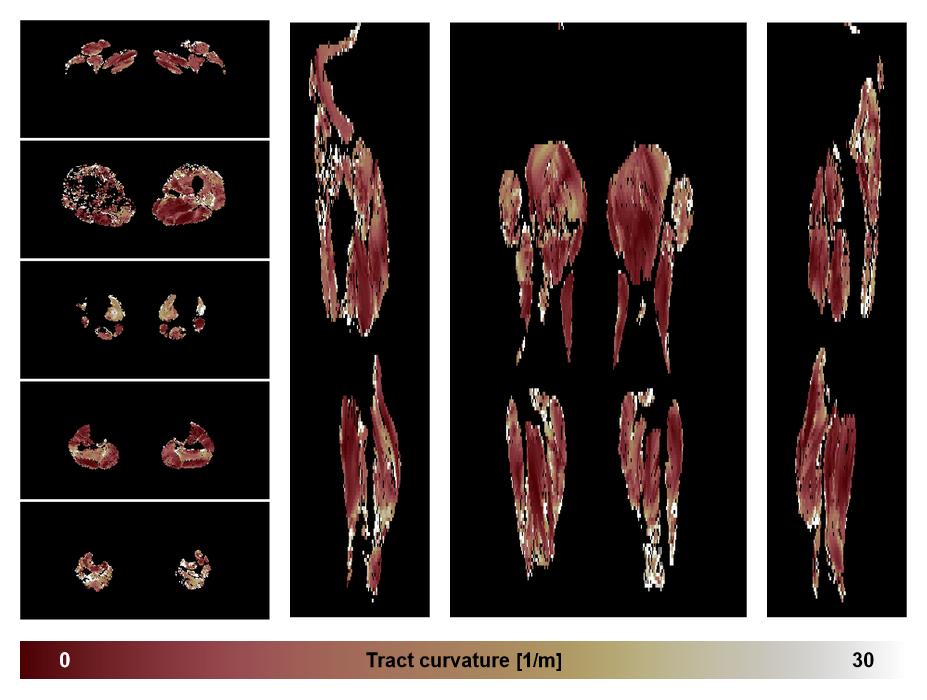

• Muscle fiber curvature map

Muscle fiber tract curvature map based on whole leg DTI based fiber tractography.